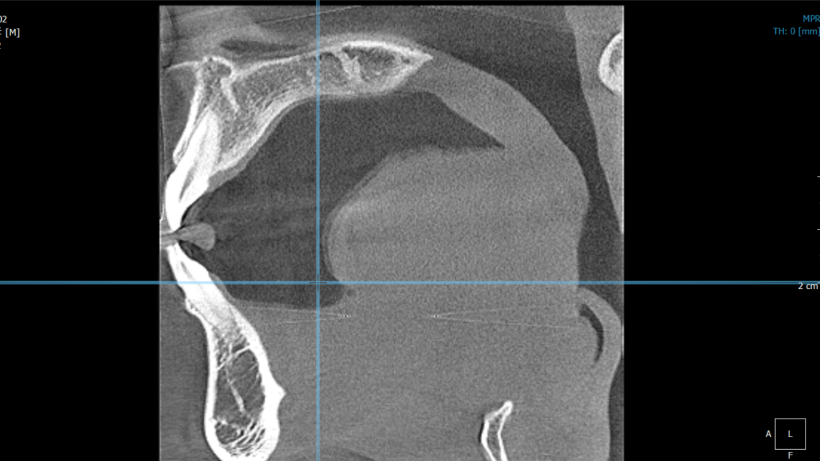

実際のCT撮影を行ったデータがこちらです。(頭部エックス線規格写真の時と同じく私です)

スライス画像をPC上で構築したものは、見たいところを見たい角度で確認することができます。2枚の写真は何を見ているのかというと、歯の顎の骨に入り込んでいる歯根(しこん)の位置を見ています。

歯は歯根を通じて顎の骨の中にあり、骨の厚みは年齢、性別、人種、また歯の場所によって異なります。インビザライン矯正治療で歯を動かしていく際に、効率的な移動の計画を立てたり、綺麗な歯並びだけでなく、長期安定を期待できる歯並びを確立するためにも、歯と骨の3次元的な位置関係を把握して治療計画を立てていきます。

また最初から歯根が短いケースや、局地的に、もしくは全体的に骨の吸収があったり、奥歯であれば親知らずと奥歯の位置関係が近接していたり、種々の解決する必要がある情報を把握しておく必要があります。